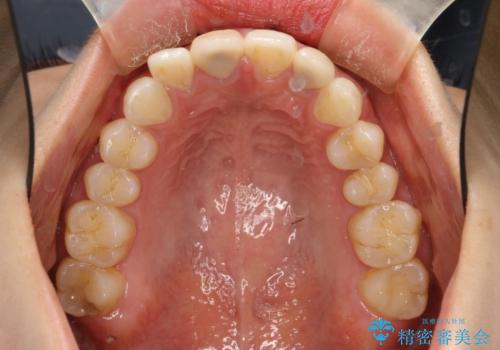

後戻りした歯並びをきれいにしたい

- ワイヤーで矯正した後戻りをマウスピースで治そうとしたが、使えなかったため再度ワイヤー矯正希望で来院されました。

装置はハーフリンガルを選択しています。

矯正としてはマウスピースでできましたが、患者さんの希望でワイヤー(ハーフリンガル)で矯正を行いました。

右下1が歯肉退縮していたため、アーチを拡げないように歯と歯の間を削って隙間をあけて並べています。